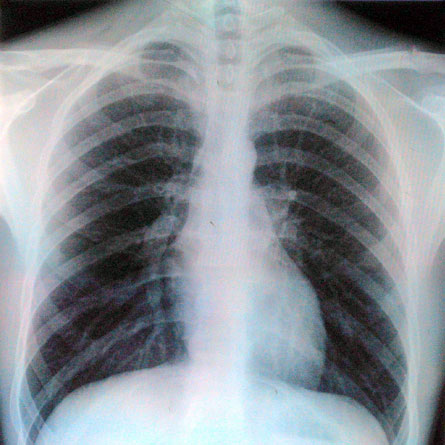

ORLANDO, Fla. — The first large study to examine cumulative radiation exposure from medical imaging after a heart attack has found that the average patient receives the equivalent of about 725 chest X-rays before leaving the hospital. That’s about one-third the maximum radiation dose allowed for a nuclear power plant worker in a given year.

To gauge how the radiation adds up, Kaul and his colleagues analyzed data from more than 64,000 patients treated in 49 hospitals throughout the United States over more than three years. The researchers reported that the average patient undergoes about four tests during each stay — most often chest X-rays, cardiac catheterizations and CT scans. Taken together, these tests expose each patient to about 14.5 millisieverts of radiation before checking out of the hospital. That is about five times the dose that an average person experiences each year. For safety, nuclear power plant workers are limited to 50 millisieverts annually.